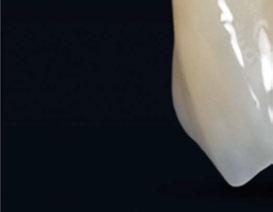

Figura 34. Rehabilitación superior impresa en resina Bego VarseoSmile TriniQ® lista para atornillar. Se han anulado de la oclusión aquellos implantes que no obtuvieron una estabilidad primaria superior a 35 N/cm2 Figura 31. Escaneado intraoral postcirugía. Figura 32. Rehabilitación recién impresa a través de impresora Varseo XS con resina Bego VarseoSmile TriniQ®. Figura 33. Ajuste pasivo entre aditamentos protésicos y la rehabilitación impresa.

aproximadamente una hora y media. Usamos resina Bego VarseoSmile TriniQ® para puentes definitivos. Aunque en este caso la vamos a usar para confeccionar unas prótesis fijas atornilladas provisionales de larga duración, dado al aumento de dimensión vertical que vamos a realizar a la paciente, de esta forma obtendremos una neuroprogramación de la ATM reinstaurando una Dimensión Vertical apropiada y mejorando la estética facial de la paciente. Excluimos de la carga aquellos implantes que no obtuvieron una estabilidad primaria superior a 35 N/ cm2. El material permite la realización de una carga inmediata en material definitivo en puentes (Figuras 31 a 38).

Figura 36. Carga inmediata provisional recién atornillada.

Figura 37. Resultado final visión frontal. Figura 38. Resultado final visión lateral.